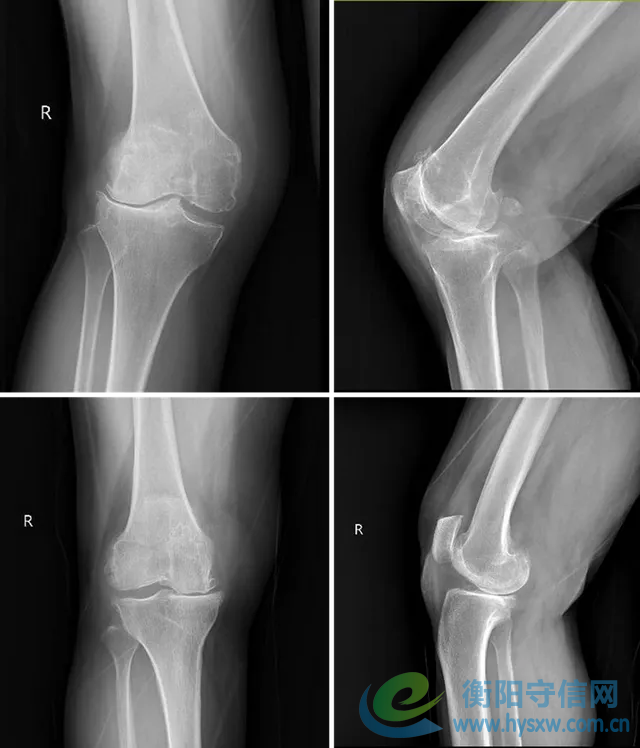

两位年过七旬的阿姨膝骨关节炎已伴随她们几十年,分别出现了膝关节严重的外翻与内翻畸形,上下楼梯钻心的疼、走几步路就得歇、连日常下蹲都成了“奢望”。随着病情加重,关节畸形、活动受限彻底打乱了她们的生活节奏,“能好好走两步”成了她最迫切的心愿。

手术当日,手术室的高清屏幕上,两位阿姨膝关节的3D建模数据清晰呈现:从截骨角度到平衡屈伸间隙,从假体型号到安装位置,每一项参数都经过术前精准测算。将术前畸形的膝关节通过机器人准确截骨完美地实现了内外侧间隙在屈伸过程中的平衡。